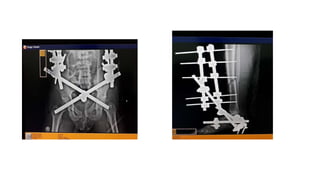

TYPES OF EXTERNAL FIXATORS

• Unilateral frame:This is the simplest external fixator frame. Four pins

two above and two below the fracture site are passed through the

bone and fixed to the frame.

• Bilateral frame: This improves the frame stiffness and helps in better

control of bending and torsional forces